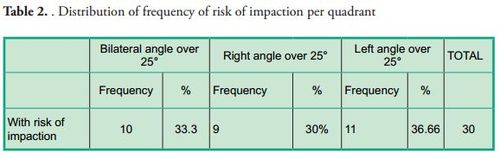

Patients with probability of eruption failure amounted to 1.43% of the sample, their mean age was 10 ± 1.7 years, and 73.3% of them were female. The variable used to determine the probability of success or failure of eruption was the angle of the second molar: an angle equal to or smaller than 24° showed probability of successful eruption, whereas an angle equal to or greater than 25° was considered with probability of eruption failure according to the average established by Evans in 1988 (average of 25° with a range from 15° to 65°). Tables 1, 2 and 3 show the results of the variables studied and their relation with the probability of teeth eruption or noneruption, unilateral or bilateral presence and distribution per quadrant.

The prevalence of risk of impaction of the lower second molar is low. The invasion of the distal face of the first molar in this study was greater than what was found in other studies. Risk of unilateral impaction is more frequent. Greater frequency of risk of impaction was found on the left side. No correlation was found between the size of the distal space of the first molar and the front edge of the ramus, and the risk of impaction of the second molar.